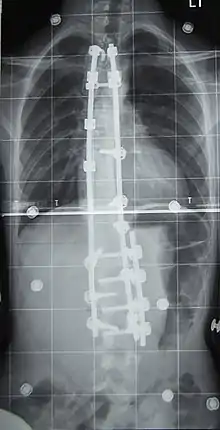

Preoperative (left) and postoperative (right) X-ray of a person with thoracic dextroscoliosis and lumbar levoscoliosis: The X-ray is usually projected anteroposterior, such that the right side of the subject is on the right side of the image; i.e., the subject is viewed from the rear (see left image; the right image is seen from the front). This projection is typically used by spine surgeons, as it is how surgeons see their patients when they are on the operating table (in the prone position). This is the opposite of many Chest radiographs, where the image is posteroanterior, i.e. projected as if looking at the patient from the front. The surgery was a fusion with instrumentation.